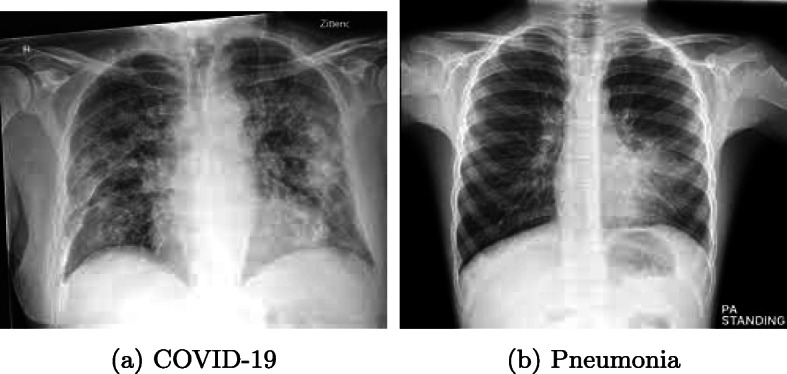

The composition of the dataset is narrated in Table 3. There are 220 numbers of CXR images were selected for this work and divided into 80:20 ratios, where 80%, 20% of data were used for both training testing respectively. The dataset is balanced and consists of 50% of images positive category (110 images) and 50% of images in are negative category (110 images). There are 120 male patients and 65 female patients. The average age of the COVID-19 cluster is 55.5 years. The training and testing dataset comprise 176 and 44 number of CXR images respectively. Due to variation in dimension in images, all were resizing to 224 × 224. Different types of CXR images from the dataset have been represented in Fig. 3. The COVID-19 CXR image (Fig. 3(a)) manifests with diffuses of the lung due to whiteness while the Pneumonia CXR image (Fig. 3(b)) depicts an area of lung inflammation and focal lobar consolidation.

Fig. 3.

Different samples of CXR image